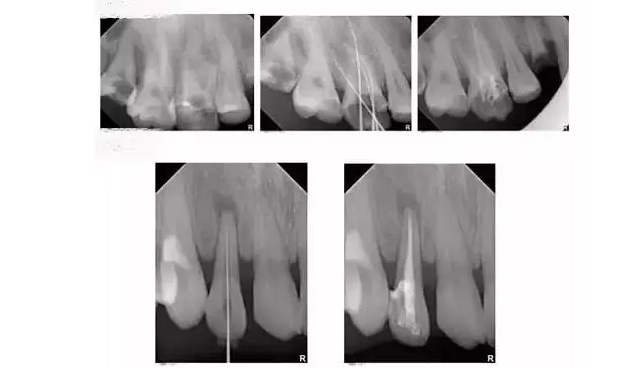

為什么根管治療需要拍多張片?

根管治療時,拍牙片是必要的,并且至少要保證3張牙片。

第一張:在治療前,幫助醫(yī)生了解牙根的基本情況,如根管預(yù)備是否到位等,并制定計劃。

第二張:在治療中,幫助醫(yī)生了解治療情況,如根管預(yù)備是否到位等,并指定下一步的計劃。

第三張:在治療結(jié)束后,幫助判定根管填充質(zhì)量,發(fā)現(xiàn)問題及時補(bǔ)救。